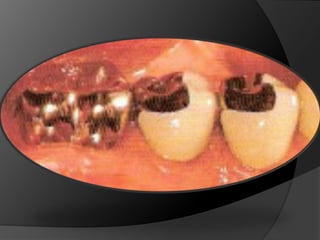

fundamentos de periodoncia en prótesis fijaCuando, por la evolución de lesiones de caries, fracturas, o necesidad de ganancia de retención mecánica en pilares muy cortos, el espacio biológico es violado, existe la necesidad de restablecer sus dimensiones, como una forma de recuperar la salud del periodonto y de facilitar los procedimientos protésicos

fundamentos de periodoncia en prótesis fijaCirugía de Alargamiento CoronalExtrusión OrtodónticaTécnica Combinada

Cuando se cuenta con la suficiente estructura dentaria coronaria para retener y proteger una restauración bajo las fuerzas previstas de la masticaciónINTEGRIDAD ESTRUCTURAL

Estructura coronaria insuficiente para retener la restauración dentro de la corona del dienteEstructura dentaria defectuosa o socavadaModificar los contornos para mejorar la oclusión o la estética